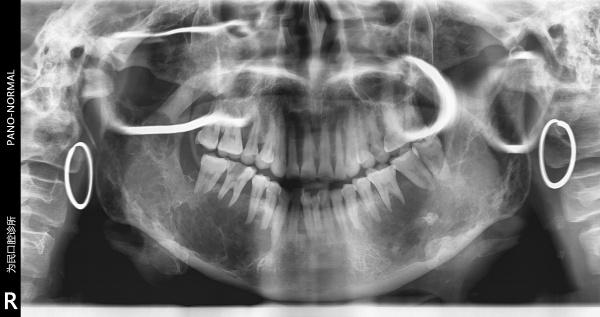

恶性造釉细胞瘤??

从医16年第一次遇见如此巨大的下颌骨破坏病例 下颌骨1